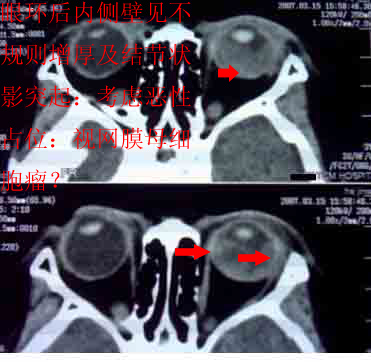

患者,偶然发现左眼无光感,平时,无明显不适,眼外观无明显异常。

首先考虑视网膜母细胞瘤。

支持左侧视网膜母细胞瘤,可惜没有钙化。

大家有没有想到有哪些需同成视网膜细胞瘤鉴别诊断的疾病?正是没有钙化,所以此病首先更应该考虑什么?请大家说说看。

ct检查:(1)眼内高密度肿块:(2)肿块内钙化斑,30~90%病例有此发现可作为诊断根据;(3)视神经增粗,视神经孔扩大,说明肿瘤向颅内蔓延。

考虑左侧眼球渗出增殖性视网膜炎所致视网膜剥离,建议mri检查。

1.ct表现:眼球内均匀高密度肿块,有增强,并多有点状或团块状钙化,在3岁以下的儿童有极大的诊断价值。可见相关视网膜下积液。

鉴别诊断 :需与渗出性视网膜病鉴别。